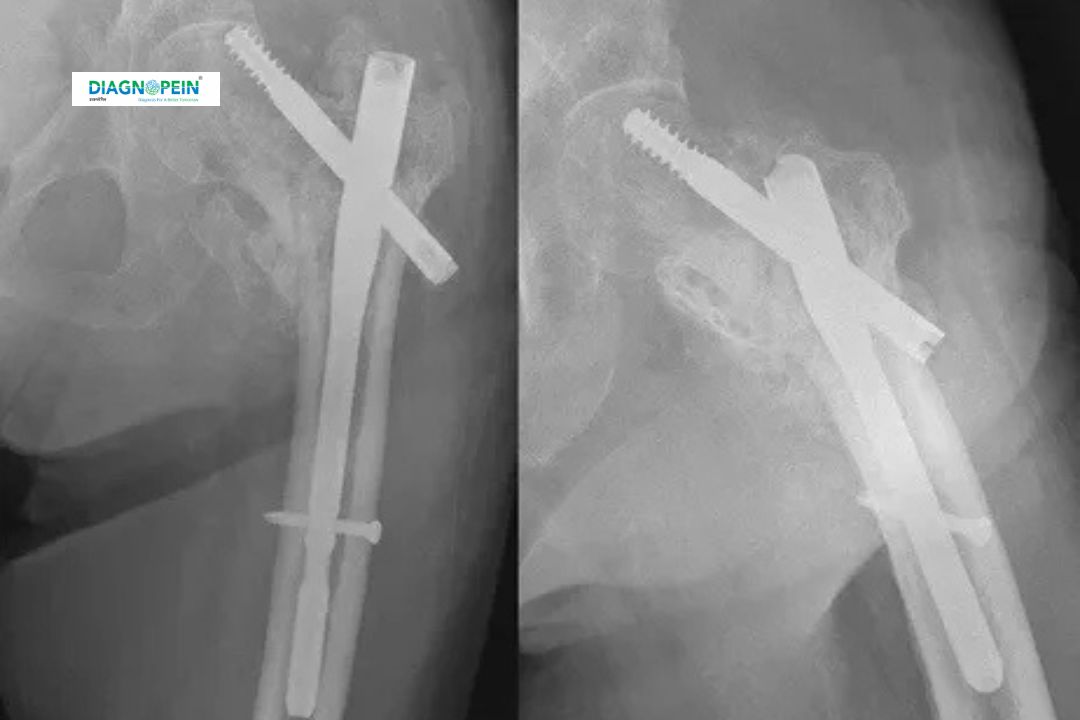

HIP AP/LAT View is a specialized X-ray examination used to visualize the hip joint, including the femoral head, acetabulum, and surrounding bone structures. This diagnostic test includes two main projections: the Anteroposterior (AP) View and the Lateral (LAT) View. Together, these views help radiologists get a clear understanding of bone alignment, joint space, and any possible deformities or fractures.

The HIP AP/LAT View X-Ray plays a vital role in diagnosing a wide range of orthopedic and musculoskeletal conditions. The AP View gives a straight-on image of the pelvis and both hips, while the Lateral View provides a side-by-side look, allowing deeper visualization of overlapping structures.